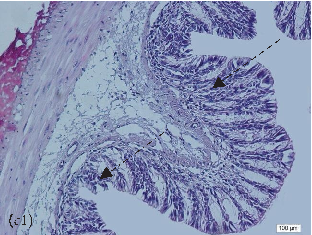

- FIGURE 2: Histopathological analysis of the colon related tothe experimental group: control group(a, a1), colitis group (b, b1),andN-acetylcysteine (NAC) group (c, c1). Representative photomicrographs of mouse colonic sections. Black arrow, preservation of the crypt structure; black dashed arrow, crypt destruction; and black dotted arrow, narrowing of the mucosal muscle. 10x magnification. Hematoxylin and eosin (HE) staining.

- 3.1. Histological Analysis of the Colon. Histological evaluation showed changes in colon architecture related to colitis, including destruction, disarrangement, and shortening of the crypts, indicating that the administration of DSS induced UC in mice (Figure 2(b)), when compared to the control (Figure 2(a)). NAC administration partially restored the epithelial structure, as indicated by the intact areas in the histological section (Figure 2(c)).